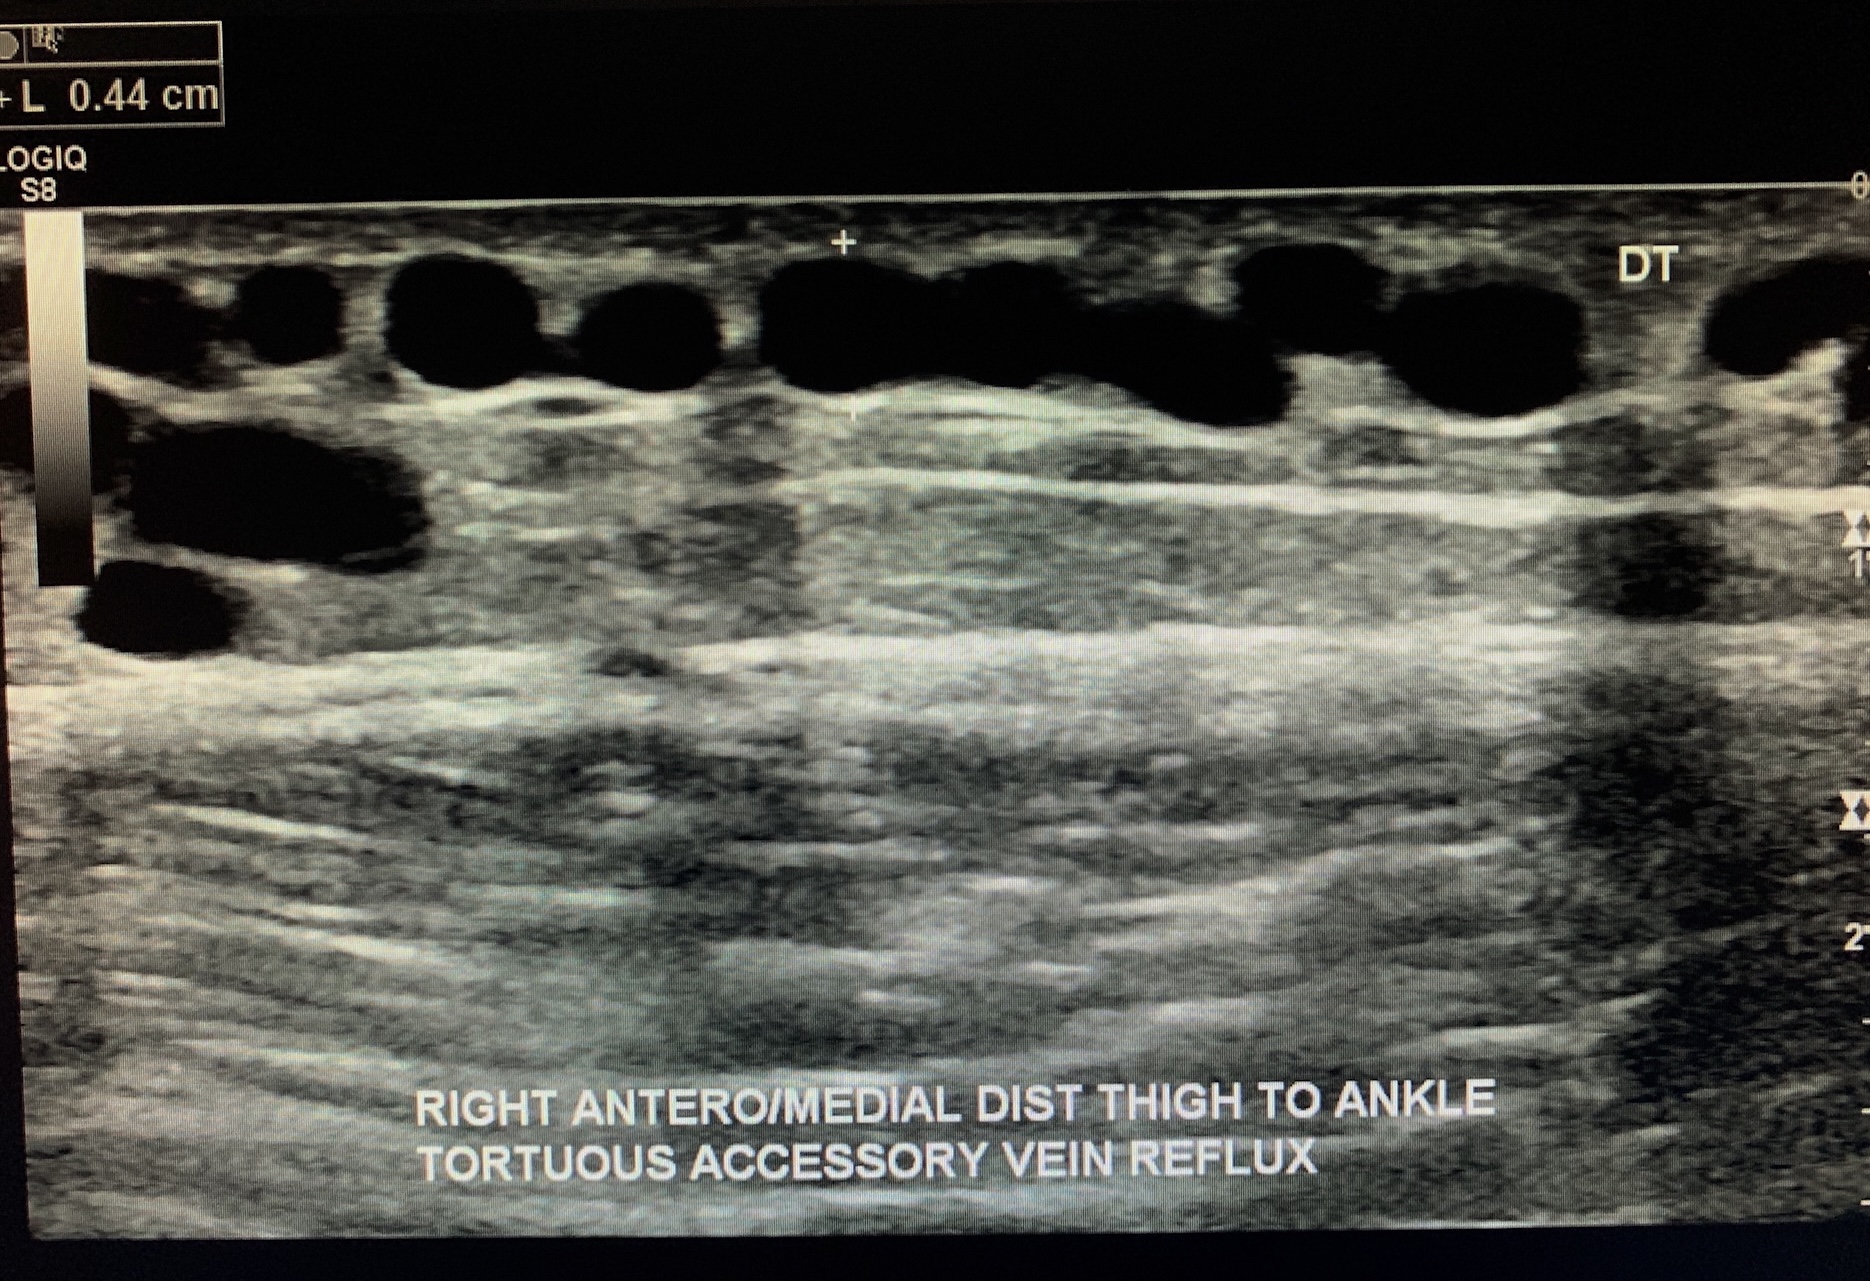

Identify an accessory vein (tributaries of the GSV) for incompetence.

Note: these are often seen as the “varicose veins” in the calves.

This incompetent accessory vein was seen as tortuous vessel from the distal thigh to the ankle

measuring approximately 4.4mm in A/P diameter w/ approximately over 3 seconds of reflux

(flow seen above the baseline)